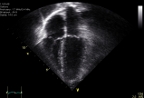

La ecocardiografía de ejercicio predice mortalidad y eventos cardiacos graves en pacientes con ergometría normal

El desarrollo de alteraciones de la contractilidad segmentaria inducidas por el ejercicio en pacientes que no desarrollan dolor torácico ni cambios en el electrocardiograma durante una prueba de esfuerzo convencional permite identificar un subgrupo de pacientes con mayor riesgo de eventos durante el seguimiento